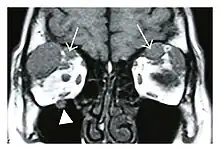

The extent of inflammation that can occur in IgG4-ROD is well demonstrated on magnetic resonance imaging (MRI).

Infraorbital nerve enlargement (IONE) is considered to be a particularly suspicious sign of IgG4-ROD, but seems to occur only when inflammation is in direct contact with the infraorbital canal.[10] IONE is defined as the infraorbital nerve diameter being greater than the optic nerve diameter in the coronal plane.

![]() Bilateral supraorbital nerve enlargements (arrows) and right infraorbital nerve (arrow head) enlargement in a 47-year-old woman with a serum IgG4 of 1000 mg/dL.[1] (T1-weighted MRI) |